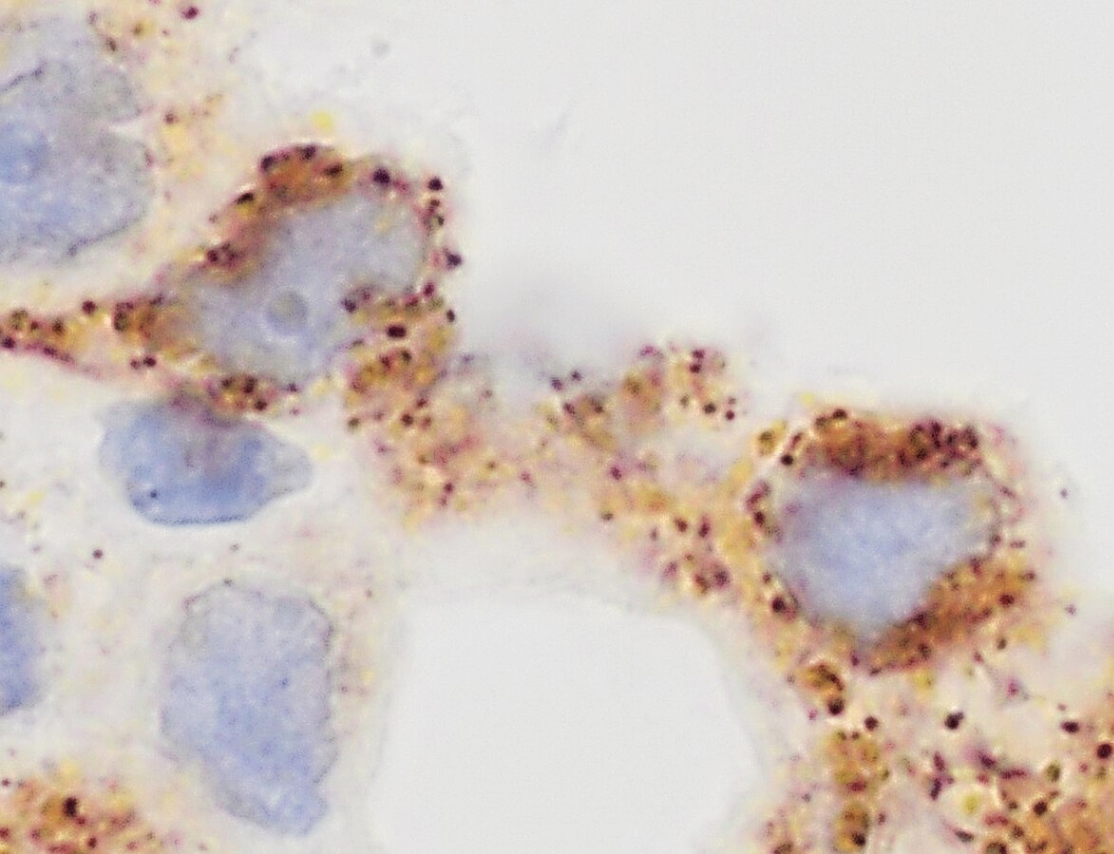

3. Immunohistochemistry (IHC)

• 목적: 조직 내 특정 항원(단백질)의 분포 및 발현 패턴 분석

• 원리:

- 조직 절편에 항체를 적용 → 항체-항원 결합

- 효소(예: HRP) 또는 형광물질이 연결된 2차 항체로 시각화

- Diaminobenzidine(DAB) 등을 사용하여 색 반응 유도

• 용도:

- 종양 진단 및 기원 조직 분류

- ex. ER, PR, HER2 (유방암), TTF-1 (폐선암), PSA (전립선암)

- 감염 병원체 항원 검출

Immunohistochemistry of adenocarcinoma with cytoplasmic staining for TTF-1, Wikimedia Commons